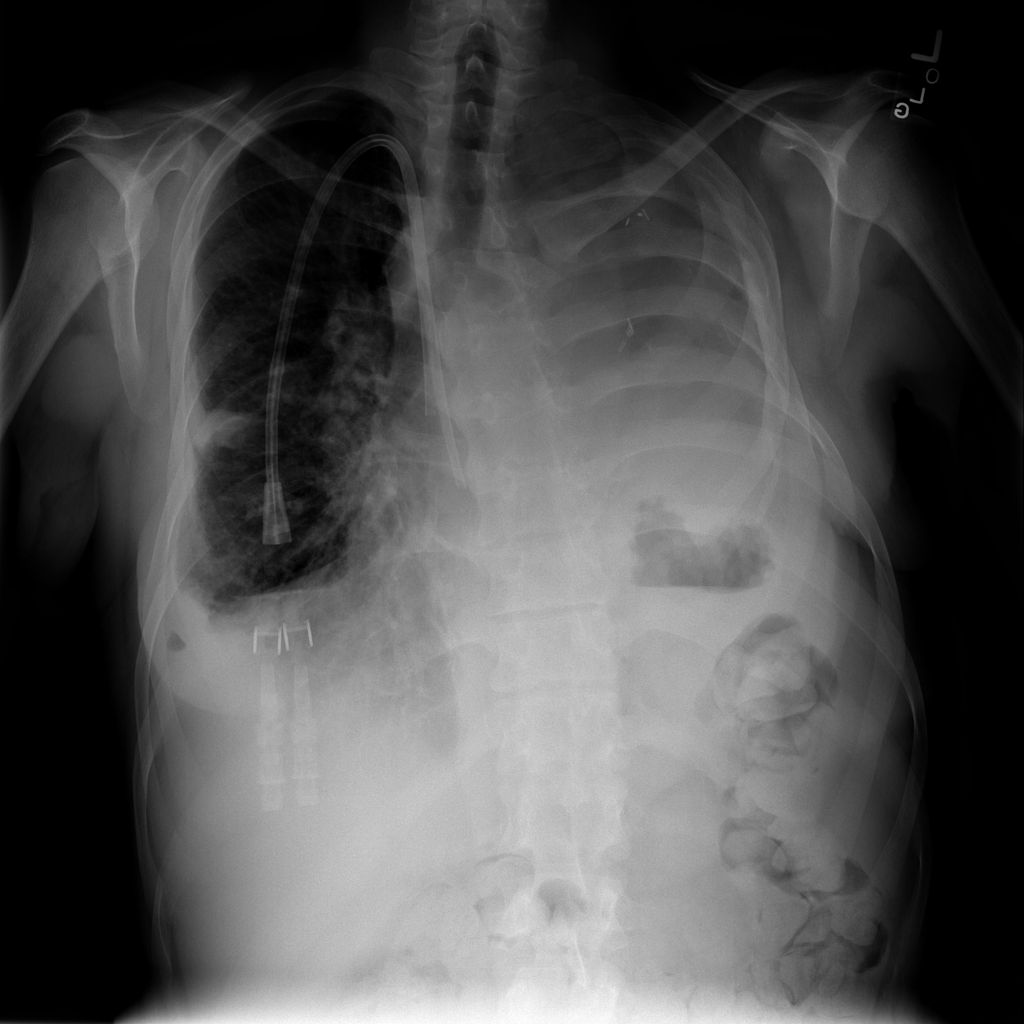

PAT-4639 · IMG-021Effusion

PAT-4639 · IMG-021

PA